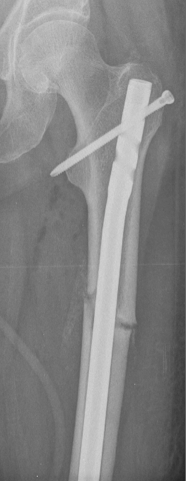

Atypical femoral fractures are rare and atypical thigh-bone fractures that have been associated with anti-osteoporosis medications that inhibit bone breakdown. The causes of these fractures are not yet known. If we can understand what factors lead to the development of these fractures, we can try to prevent them. Nevertheless, the benefits of anti-osteoporosis medications to reduce broken bones due to osteoporosis far outweigh the small risk of an atypical femur fracture.